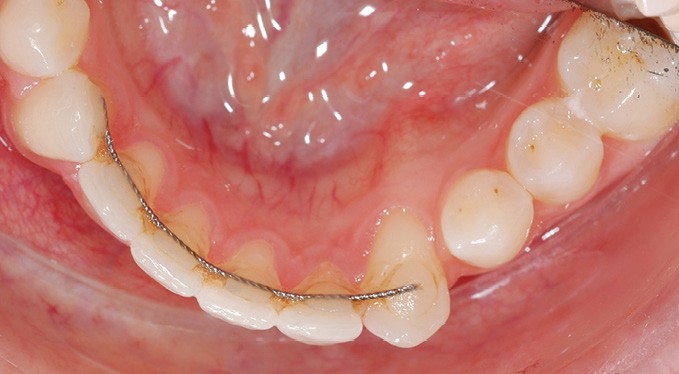

Par exemple, le retraitement d’un patient atteint d’un « Syndrome du fil » [2, 3], au vu de l’état des connaissances imparfaites de l’étiologie de cette situation, méritera une réflexion pour trouver un système de confiance. Une fibre collée est l’une des solutions sécurisantes (fig. 1). Mais, si la langue n’est pas stabilisée au repos comme en fonction, un dispositif amovible type Spring Retainer sera préférable.